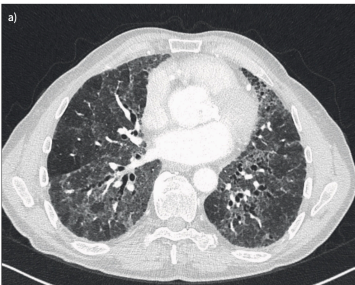

HRCT findings chronic HP

Diffuse centrilobular nodules

GG

Mosaic attenuation

+- honeycombing, traction bronchiectasis